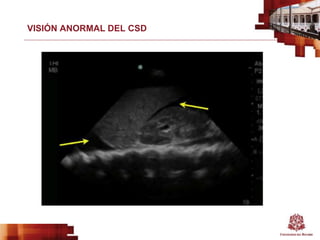

VISIÓN ANORMAL DEL CSD